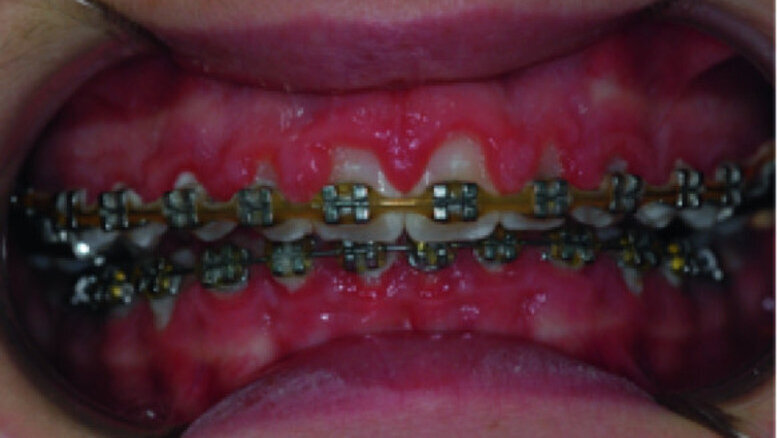

Surgical laser-assisted treatment via laser gingivectomy.

A 14-year-old female patient was referred to our department by the orthodontics unit because, at the end of fixed orthodontic treatment, she had developed gingival enlargement in the upper arch (Fig. 1), probably related to the fast closure of the spaces associated with very poor oral hygiene due to bleeding during toothbrushing. Just after the removal of the appliance, a topical anaesthetic (EMLA, AstraZeneca) was applied to the gingivae (Fig. 2) and a gingivectomy was performed using a diode laser (XD-2, Fotona) according to the technique of removal of the inter dental papillae (Fig. 3). The parameters used were as follows: a wavelength of 808 nm, 3 W in continuous wave, a 320 μm fibre in contact mode. The intervention had a duration of 375 seconds, and the patient did not feel any pain (Fig. 4). After the intervention, the patient did not take any kind of pain medication, and the healing process was completed in five days (Fig. 5).